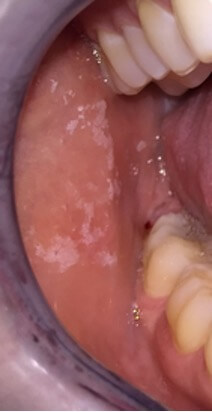

Fig. 7.

Candidiasis of the inner mucosa of the cheeks in a woman, due to inhaled corticosteroids treatment (Becotide®, GSK, France).